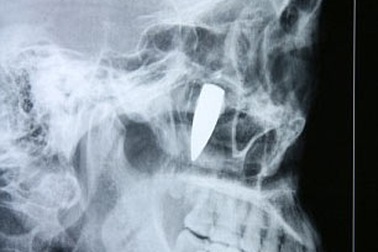

Gắp viên đạn nằm trong gò má 42 nămBà He Wenying (Trung Quốc) đã quyết định phẫu thuật gắp viên đạn nằm ở gò má, gần hốc mắt - thủ phạm gây ra chứng đau đầu kinh niên mà bà đang phải chịu đựng suốt 42 năm qua.